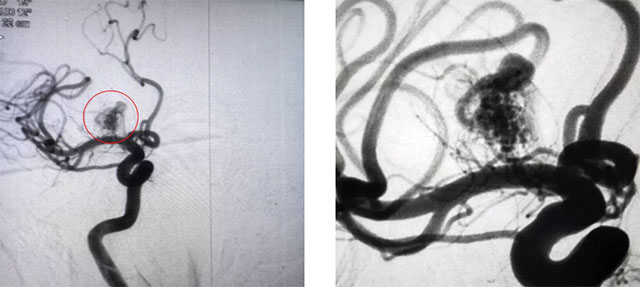

▲ 患者腦動(dòng)靜脈畸形DSA顯像圖(栓塞前后)

患者兩周前突發(fā)頭痛,腦血管CTA:右側(cè)前顱底語氣團(tuán)簇狀血管影。經(jīng)醫(yī)院DSA檢查,確診為功能區(qū)動(dòng)靜脈畸形。其供血?jiǎng)用}來源是大腦前動(dòng)脈的分支血管Heubner回返動(dòng)脈(功能血管),該血管與肢體活動(dòng)密切相關(guān)。該動(dòng)靜脈畸形位于功能區(qū),引流靜脈中有部分導(dǎo)入深部靜脈,畸形團(tuán)大小3cm*4cm,根據(jù)Spetzler&Martin分級(jí),綜合評(píng)分3分,屬于級(jí)別較高的畸形。

再次造影發(fā)現(xiàn)畸形團(tuán)大部分不顯影,手術(shù)順利,隨后予以撤除導(dǎo)管后封堵局部穿刺點(diǎn)。術(shù)后,患者遵囑動(dòng)作,無四肢無活動(dòng)及感覺障礙,無神經(jīng)功能缺損,手術(shù)取得成功。本次栓塞60%以上,后期出血風(fēng)險(xiǎn)相對(duì)較小,下一步可結(jié)合伽馬刀治療。